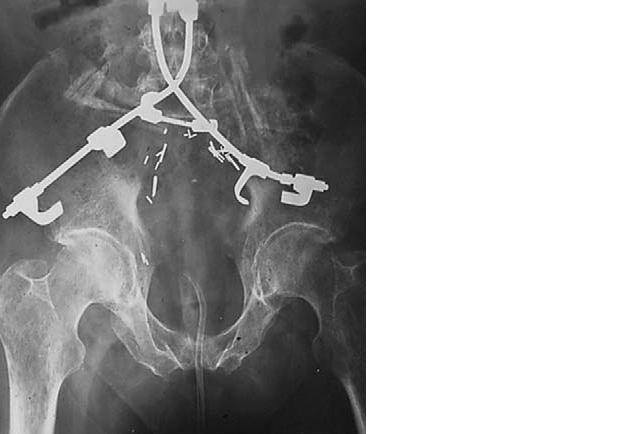

Поэтому пользуемся конструкцией, похожей на представленную на нижеуказанном рисунке.

Для бедной российской действительности альтернативу можно смастерить из 2 стержней один конец которых изгибается S-образно, затачивается и вбивается прямо в подвздошные кости (методика Гальвстона). Прксмимальную фиксацию стержней можно выполнить по Люке (совсем для бедных) или к ТП винтам. Третий вариант с крючковой конструкцией (рентгенограмма отдельной вкладкой). Лучше зафиксировать 3 поясничных позвонка.

Имя     : Илеолюмбальная фиксация.jpg

Имя     : Илеолюмбальная фиксация 2.jpg